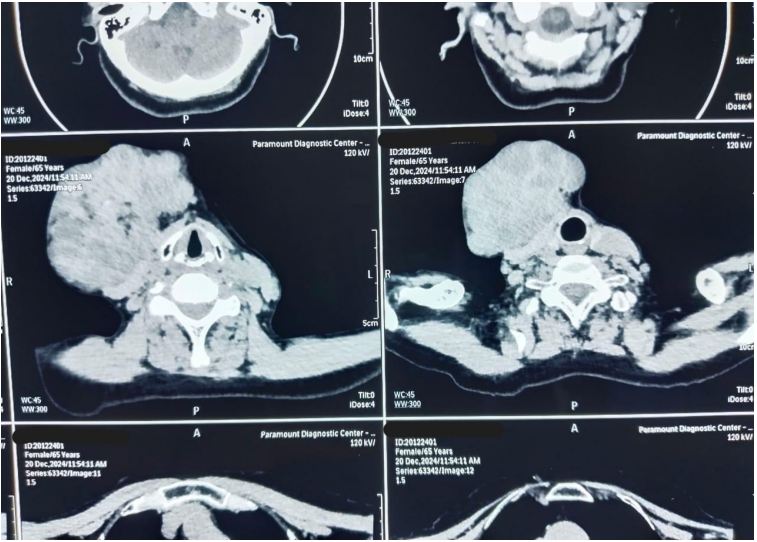

A 71-year-old female presented at Bankers Superspeciality Hospital complaining of swelling over the right side of the face and upper neck region, with localised swelling over the sternum. She was asymptomatic 5 months back as she gradually noticed swelling over her right side of her face and upper neck region, which gradually increased in size. In the past (2018), she had surgery at a local hospital, query for parotid surgery; no documents were available ( surgery note and histopathological report). On inspection and palpation, 8*7cm hard proliferative, lobulated growth present over the right side upper neck region, not fixed to underlying structures, crossing midline of the face with no ulceration present over skin (Image 1). No neck nodes were palpable. No sign of facial palsy present. Localised mass of 6*5cm was present over the right side sternum, which was fixed to the underlying bone (Image 2). No skin ulceration was present over sternum region and no axillary nodes were palpable. The performance status of the patient was ECOG 1. Computed tomography of Neck and chest (Plain + Contrast) suggestive of large heterogeneously enhancing lobulated solid cystic lesion seen in right submandibular and upper internal jugular regions and right submental region anterior to right sternocleidomastoid muscle, size of 94(W)*76(AP)*79.6(CC)mm, with mild compression on right IJV. Approx 78*75*92mm soft tissue lesion involving sternum causing osteolytic destruction extending into the anterior mediastinum displacing heart and other structures posteriorly. A few variable-sized soft tissue density nodules scattered throughout both lungs (Image 3 & Image 4). Trucut Biopsy from Right submandibular region s/o pleomorphic adenoma ( composed of epithelial tubules and myoepithelial cells in abundant chondromyxoid stroma) (Image 5 & Image 6). Trucut Biopsy from sternal mass suggestive of malignant tumor, likely to be sarcoma, chondrosarcoma is a possibility. Further Immunohistochemistry was done which suggestive of lesional cells with chondroid type appearance and matrix with positive for AE1/3, CK7 and S100 with KI-67 2-3% favouring Benign metastasizing pleomorphic adenoma (Image 7 & Image 8). PETCT scan was done, which suggestive of FDG avid heterogenously enhancing lobulated soft tissue mass involving right submandibular and submental region 8.6(AP)*7.3(TS)*8.9(CC) ; SUV max 8.6. Medially involving the Right submandibular gland Indenting onto right SCM and strap muscles, Superioly lesion is infiltrating inferior lobe of right parotid gland, overlying skin is involved with no obvious erosion. FDG avid lytic destructive lesion are noted involving sternum, left fifth rib, D12 and L3 vertebrae. Sternal lytic destructive lesion is present with soft tissue compenent with calcification of 8.2*7.2*10.5cm; SUV max 5.9. Soft tissue component is extending into anterior mediastinum and is seen infiltrating right middle lobe lung parenchyma. Left fifth rib is assosciated with  FDG avid enhancing soft tissue component 2.6*2.3cm; SUVmax 6.5 (Figure 9). On PETCT Scan report with skeletal metastasis, in multidisciplinary tumor board discussion, the case was discussed and decided to give palliative chemotherapy.

Figure 3: Computed Tomography with contrast of Head and Neck

Figure 4: Computed Tomography with contrast of Chest